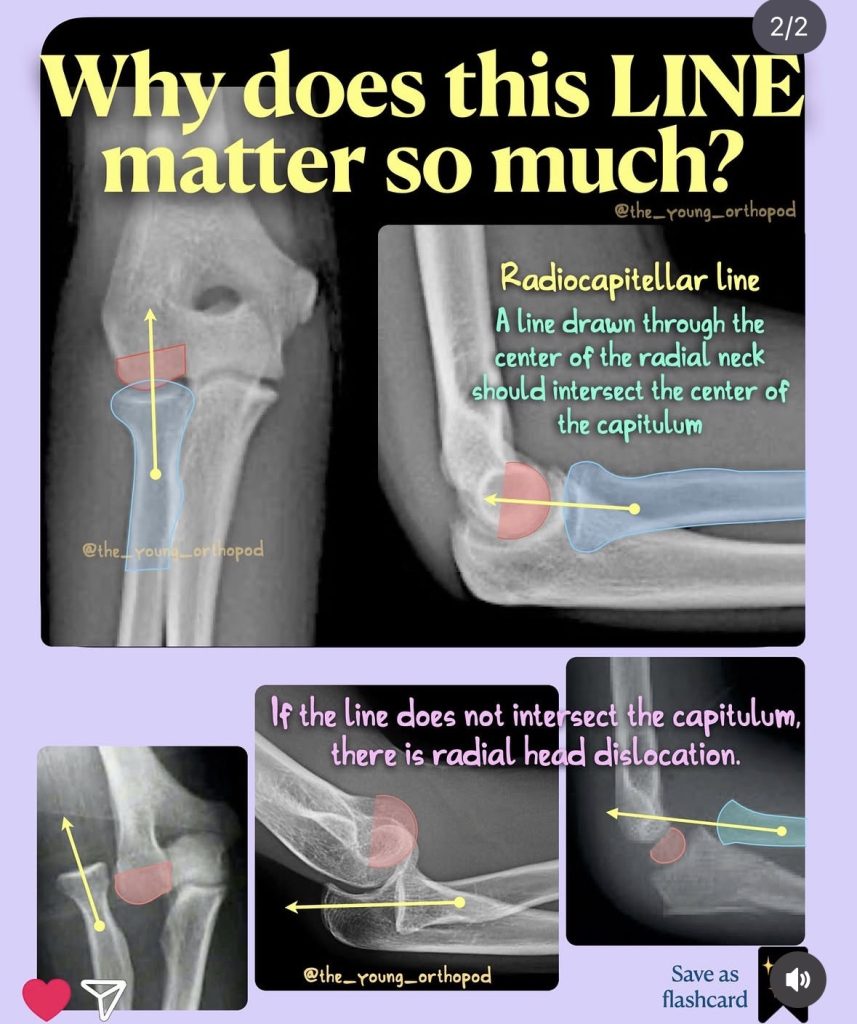

Radiocapitellar line, dirsek grafilerinde (özellikle çocuklarda) radius başı ile kapitellum hizasını değerlendirmek için kullanılan temel bir radyolojik referans çizgisidir.